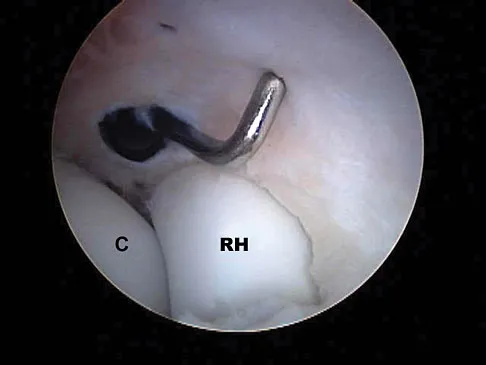

What neurovascular structure is in closest proximity to the probe in the arthroscopic view of the elbow shown in Figure 50?

The image shows a view of the radiocapitellar joint from an anterior medial portal. The radial nerve lies on the elbow capsule at the midportion of the capitellum. It is at risk for injury when capsular excision is performed in this region. Field LD, Altchek DW, Warren RF, et al: Arthroscopic anatomy of the lateral elbow: A comparison of three portals. Arthroscopy 1994;10:602-607.